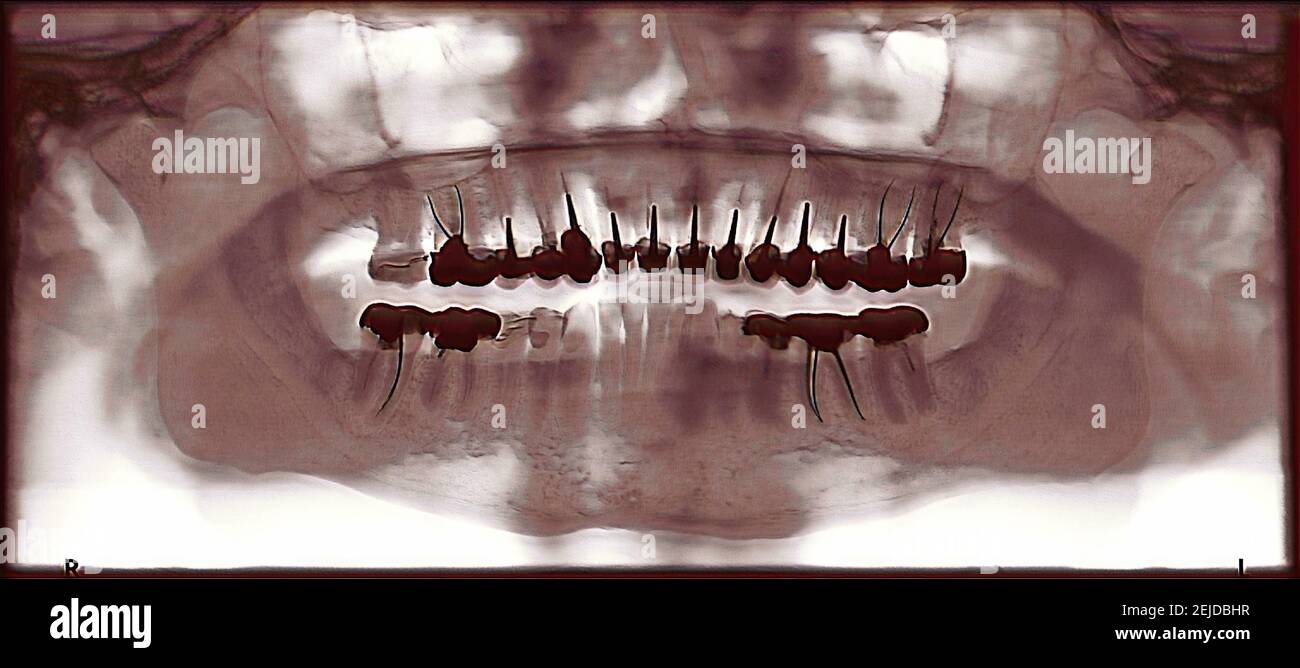

From www.alamy.com

Colorized jaw xray. Presence of dental crowns Stock Photo Alamy What Can A Jaw X Ray Show So, fillings and crowns that are made of. Jaw tumors and cysts — sometimes referred to as odontogenic or nonodontogenic, depending on their origin — can vary greatly in. It provides a detailed view of the jawbone, helping the. This is useful, as your dentist can recommend certain treatments (for example, braces, implants, or wisdom teeth removal) based on your. What Can A Jaw X Ray Show.

Colorized jaw xray. Presence of dental crowns Stock Photo Alamy What Can A Jaw X Ray Show Jaw tumors and cysts — sometimes referred to as odontogenic or nonodontogenic, depending on their origin — can vary greatly in. P athologic conditions affecting the jaw are common yet not frequently imaged or encountered by radiologists. So, fillings and crowns that are made of. It provides a detailed view of the jawbone, helping the. This is useful, as your. What Can A Jaw X Ray Show.